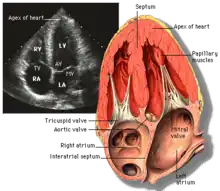

Apical four chamber ultrasound view of heart

Transthoracic echocardiography (TTE) uses ultrasonic waves for continuous heart chamber and blood movement visualization. It is the most commonly used imaging tool for diagnosing heart problems, as it allows non-invasive visualization of the heart and the blood flow through the heart, using a technique known as Doppler.

TTE is commonly used to evaluate patients with coronary artery disease.[4] Stress echocardiography is used to diagnose coronary artery disease and assess myocardial viability.[4]